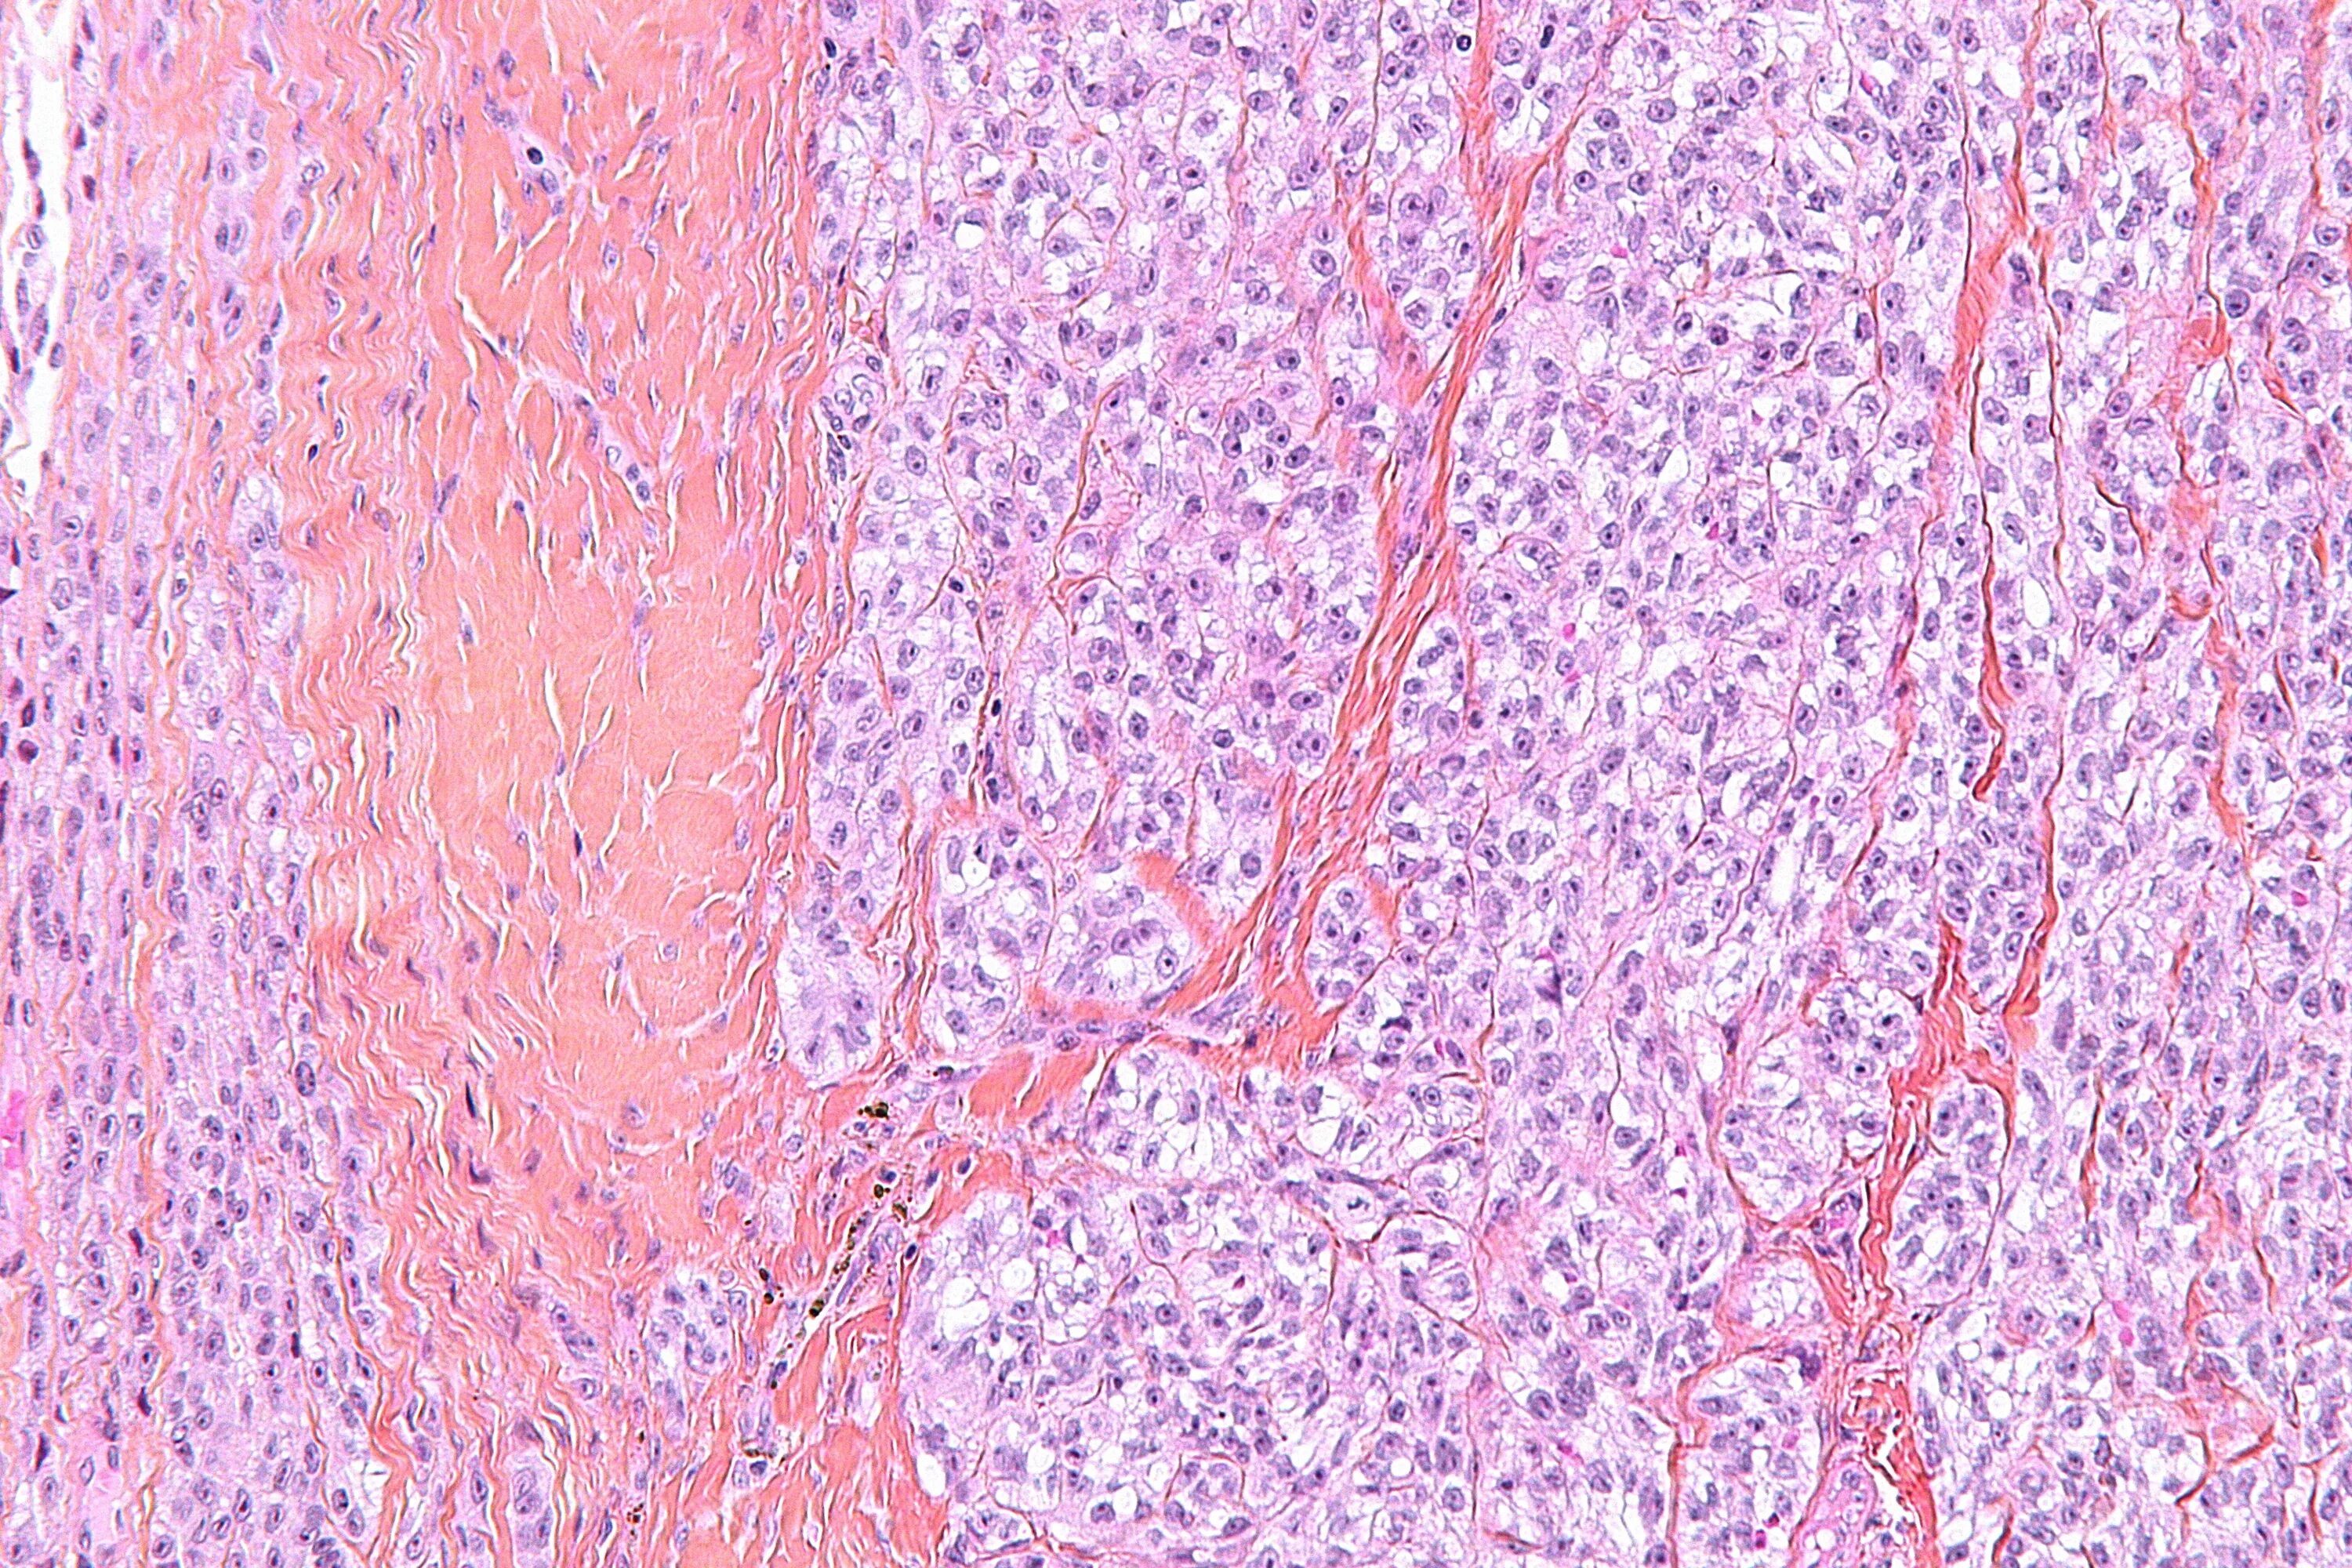

Гистологическая картина